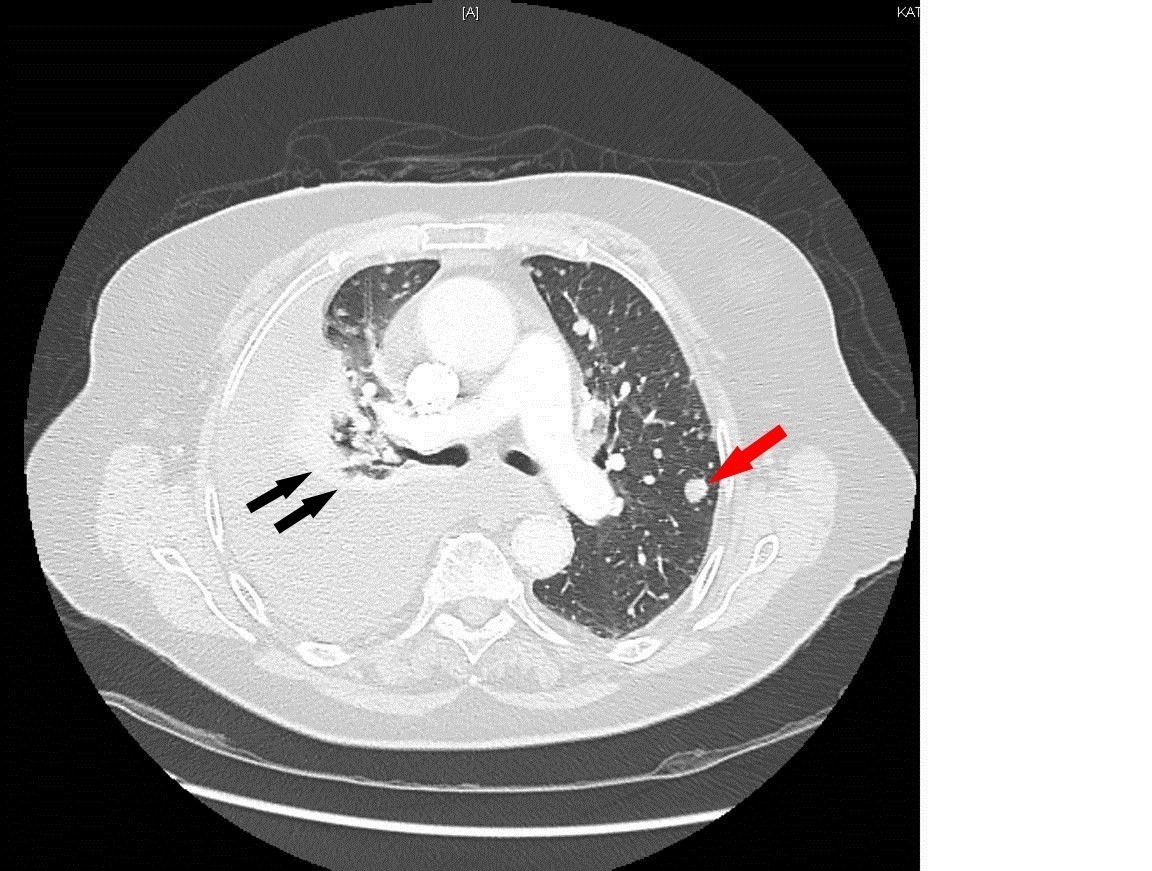

À évoquer en priorité car TVP récente et douleur thoracique. Le traitement anticoagulant en cours n’élimine pas une migration embolique (surtout en cas de mauvaise observance).

À évoquer devant une douleur thoracique latéralisée.

À évoquer devant une douleur thoracique latéralisée chez une patiente avec tabagisme important.